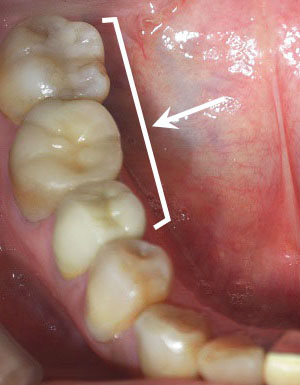

50代女性(右下5,6,7)上牧町在住

右下奥の歯を3本セラミックにかえました。